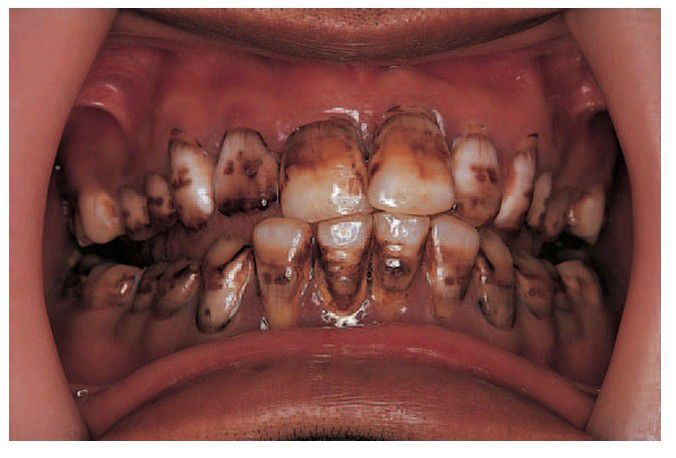

Fluorosis

. Severe effects from an area of endemic fl uorosis. Closer view showing irregular depressions caused by hypoplasia and white opaque fl ecks and patches.